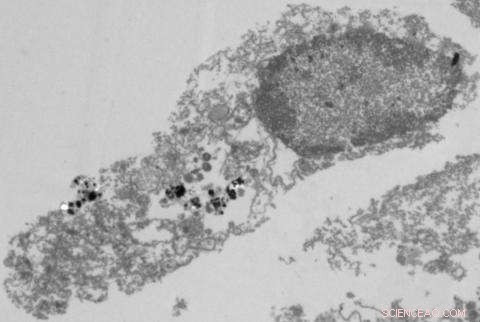

Disruption of the tumor cell due to treatment with nanoparticles and visible light.

Researchers at the University of Michigan Kellogg Eye Center have developed a new nanoparticle that uses a tumor cell's protective mechanism against itself—short-circuiting tumor cell metabolism and killing tumor cells.

"Our work uses a semiconducting nanoparticle with an attached platinum electrode to drive the synthesis of an anti-cancer compound when illuminated by light," says Howard R. Petty, Ph.D., professor of ophthalmology and visual sciences and of microbiology and immunology. "The nanoparticle mimics the behavior of NADPH oxidase, an enzyme used by immune cells to kill tumor cells and infectious agents. Since tumor cells typically use NADPH to protect themselves from toxins, the more NADPH they synthesize for protection, the faster they die."

In a four-year study conducted on the mouse model in advanced breast cancer metastasis in the eye's anterior chamber, Petty and colleagues found that the new nanoparticle not only killed tumor cells in the eye, but also extended the survival of experimental mice bearing 4T1 tumors, a cell line that is extremely difficult to kill. "Previous monotherapies have not extended the lifetimes of mice bearing this type of tumor," Petty said. "Our work has shown that we can extend survival of the mice."

"This treatment offers many advantages," Petty says. "The nanoparticle produces about 20 million toxins per hour in each cell. Also, the nanoparticle is activated by light, so it can be turned on and off simply by exposing it to the correct color of visible light."